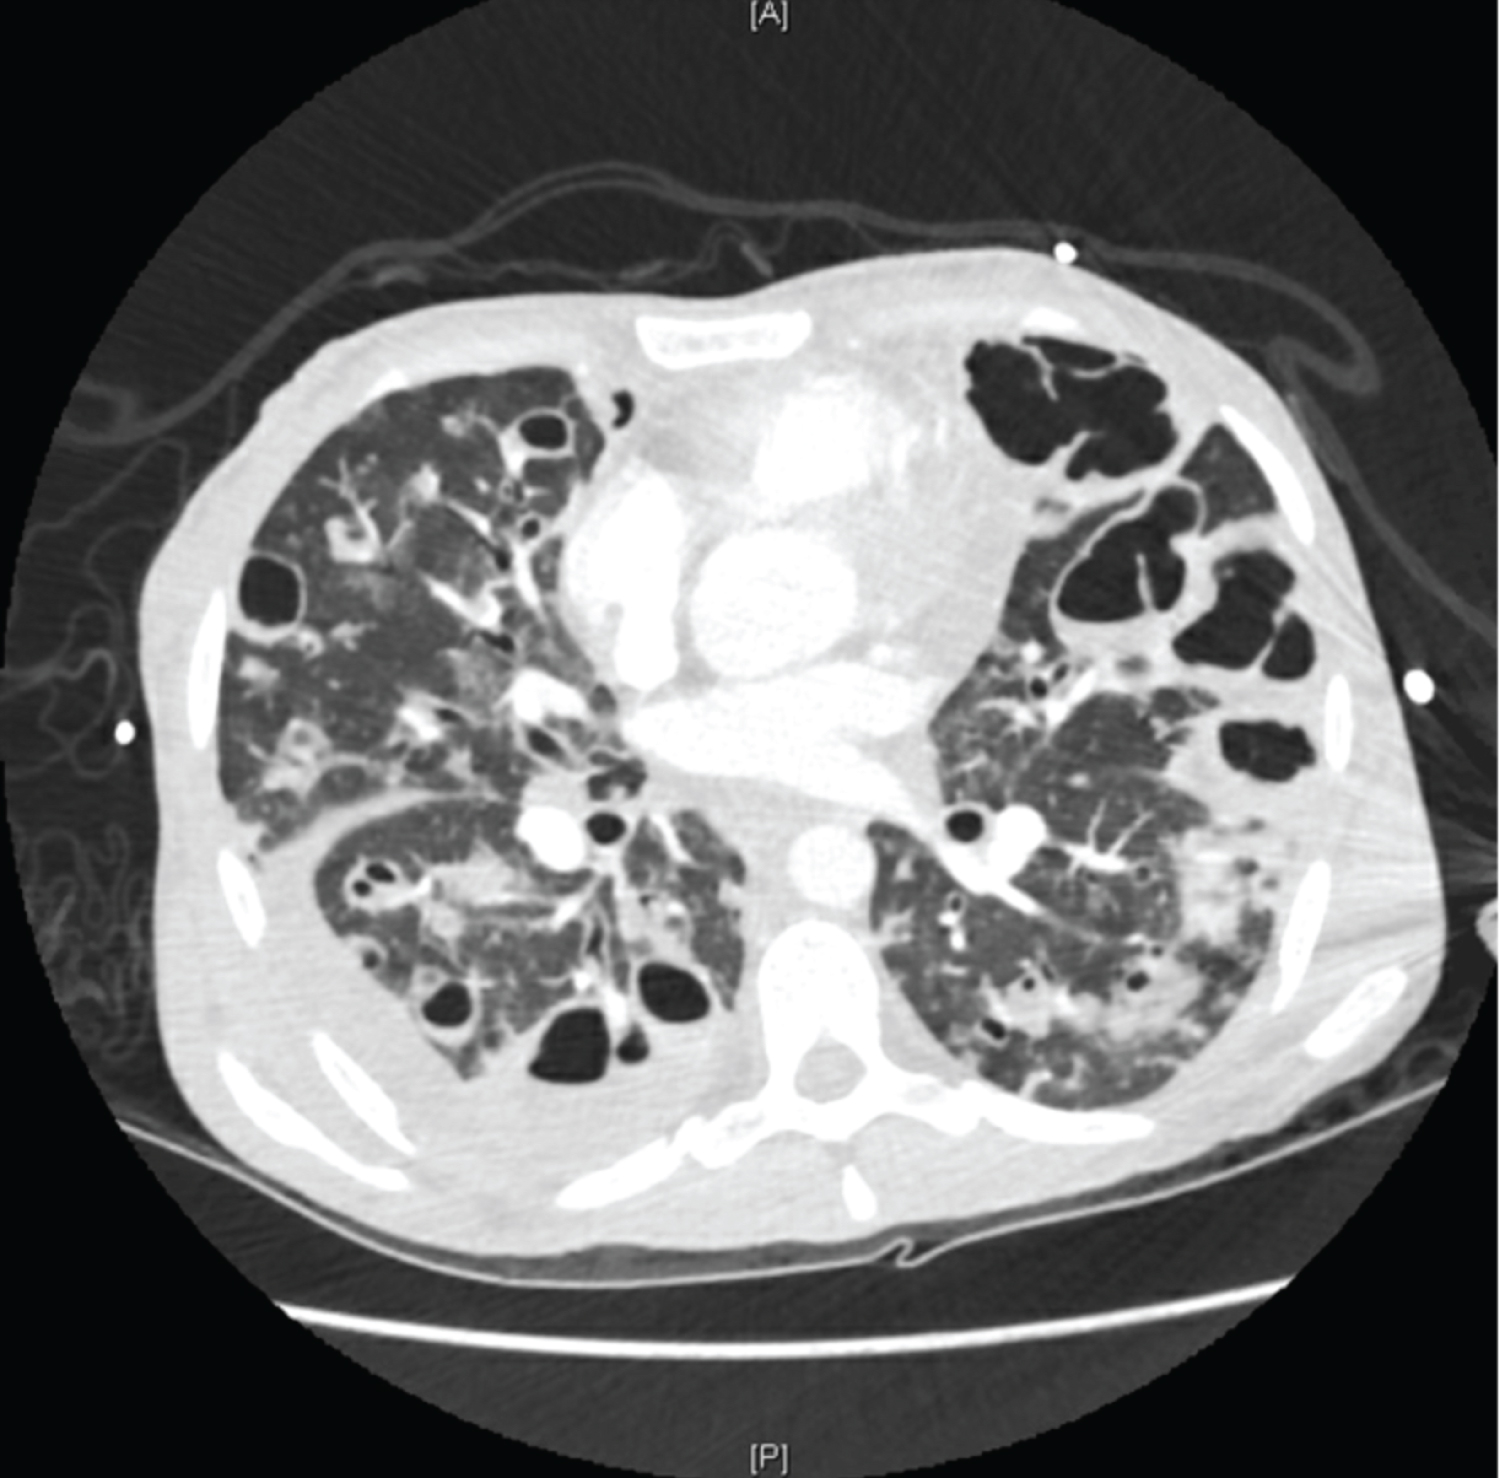

A 29-year-old female with an extensive history of polysubstance abuse presented to an outside hospital for symptoms of myalgias, malaise, and a dry cough for one week in duration. Additional imaging was obtained, most notable for multiple cavitary lung lesions, a possible bronchopleural fistula, and tricuspid valve vegetation. The patient was transferred to our institution for consideration for cardiothoracic surgical intervention. Upon arrival, the patient was found to be hypoxic with an oxygen saturation of 79% on room air, tachypneic, and tachycardic to 130 beats per minute. She presented with altered mentation and was subsequently intubated for worsening respiratory distress. A left lower sternal border diastolic heart murmur and coarse breath sounds on posterior chest auscultation were appreciated. Blood cultures obtained at the previous hospital were positive for methicillin resistant Staphylococcus aureus and reconfirmed on three subsequent sets of repeat blood cultures. CT scan findings were significant for numerous lung cavitating lesions with thickened walls bilaterally (Figures 1, Figure 2, Figure 3, Figure 4 and Figure 5), as well as bilateral renal and splenic hypodensities concerning for infarctions. Echocardiogram revealed tricuspid valve regurgitation and multiple vegetations (Figure 6). Admission complete blood count was significant for leukocytosis with a white blood cell count of 24.2k /uL, thrombocytopenia with a platelet count of 24 k/uL. All of the above findings in conjunction with history were suggestive of cavitary septic emboli from infective endocarditis. The patient developed septic shock due to endocarditis and a right pneumothorax likely secondary to a ruptured cavity (Figure 4). Cardiothoracic surgery evaluated the patient for consideration for tricuspid valve repair and deemed her to not be a surgical candidate given her pulmonary status. After a discussion with the patient's family, the patient was palliatively extubated and the patient unfortunately expired [1,2].

Figure 2: CT scan of the chest at level of pulmonary arteries.

Figure 3: CT scan of the chest inferior to the level of the pulmonary arteries with evidence of right sided pleural effusion.